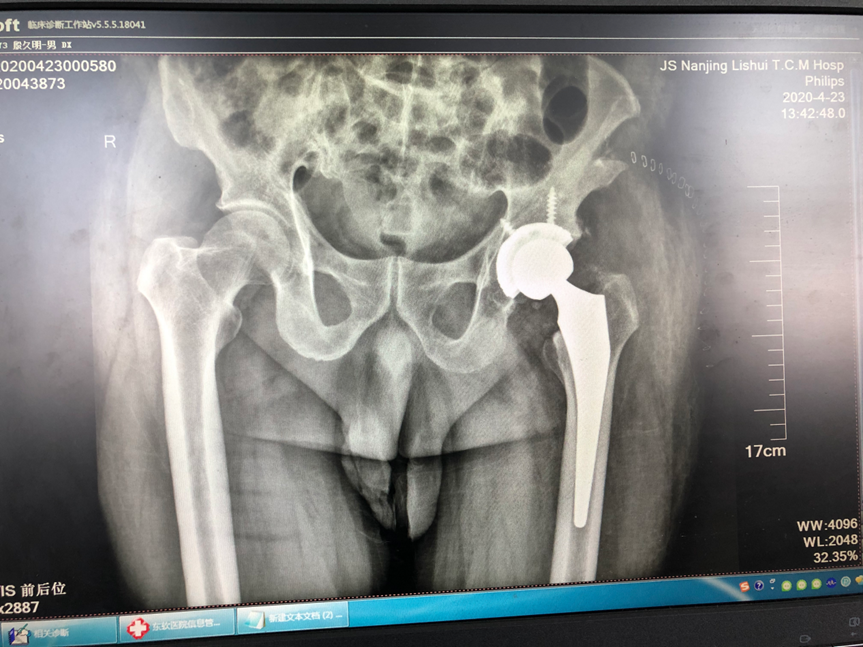

科室主任贾晋辉博士先后两次赴德国学习,在骨折微创手术,全髋关节置换,全膝关节置换,膝关节单髁置换、关节镜微创手术等方面引进当今最先进技术,已治愈了几千例患者,病人满意度很高。